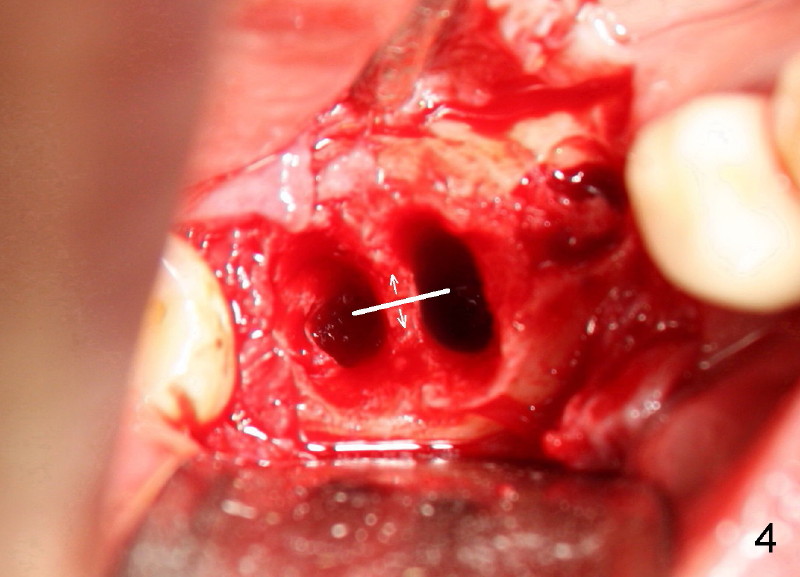

Six weeks post-extraction, a straight incision is made along the crest of #30/31. Without raising flap, #15 surgical blade, bone scalpels (4,5,6 mm wide) and bone blades (4,5.5,7.5 mm wide) ) (Fig.4 white line (illustration); Tatum Surgical) are used to expand the septum buccolingually (arrows). Then round tapered osteotomes (Fig.5 black circle (illustration)) are used to expand the septum circumferentially (arrows). Bone expansion with osteotomes alternates with sequential drills using irrigation. Fig.6 shows 4x17 and 4x14 mm drills placed in sockets #30 and 31, respectively. It appears that osteotomies are placed somewhat distally. The drill #31 is distal to the septum (*).